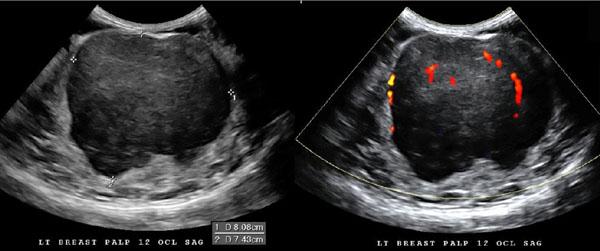

What is a simple cyst?

benign breast condition

Very common in women ages 35 to 50

Results from obstructed duct or hormonal changes

Regress after menopause

Presentation: breast lump, pain & tenderness

What is the Sonographic Appearance of simple cysts?

Oval or round

anechoic

smooth walls

well circumscribed shape

posterior enhancement

edge refraction

sharp anterior and posterior borders

reverberation

Why is Doppler helpful during a breast exam?

distinguishing

solid vs cystic - flow confirms a solid

inflamed vs noninflamed - increased flow

complex cyst vs intraductal papilloma